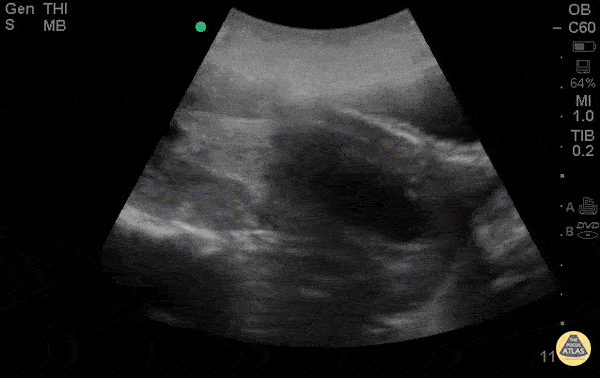

OB/Gyn - Spontaneous Abortion Sagittal

28yo F G5P4 presenting at 8 weeks pregnant by LMP for pelvic pain and vaginal bleeding for 2 days. POCUS demonstrates an anechoic gestational sac without a visible yolk sac of fetal pole, progressing past the cervix. The patient had a spontaneous abortion in the ER, passing products of conception shortly after the POCUS. Esther Kwak, MD, Ian Desouza, MD- Kings County/SUNY Downstate Emergency Medicine